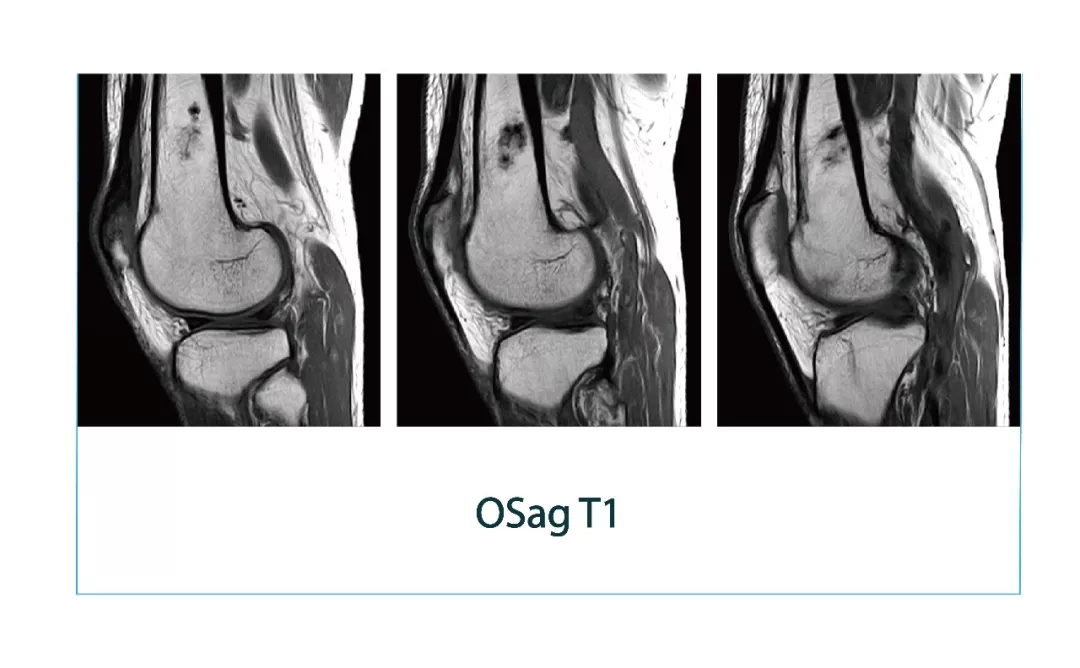

【朗润影像档案】磁共振影像病例分享(编号20180112)